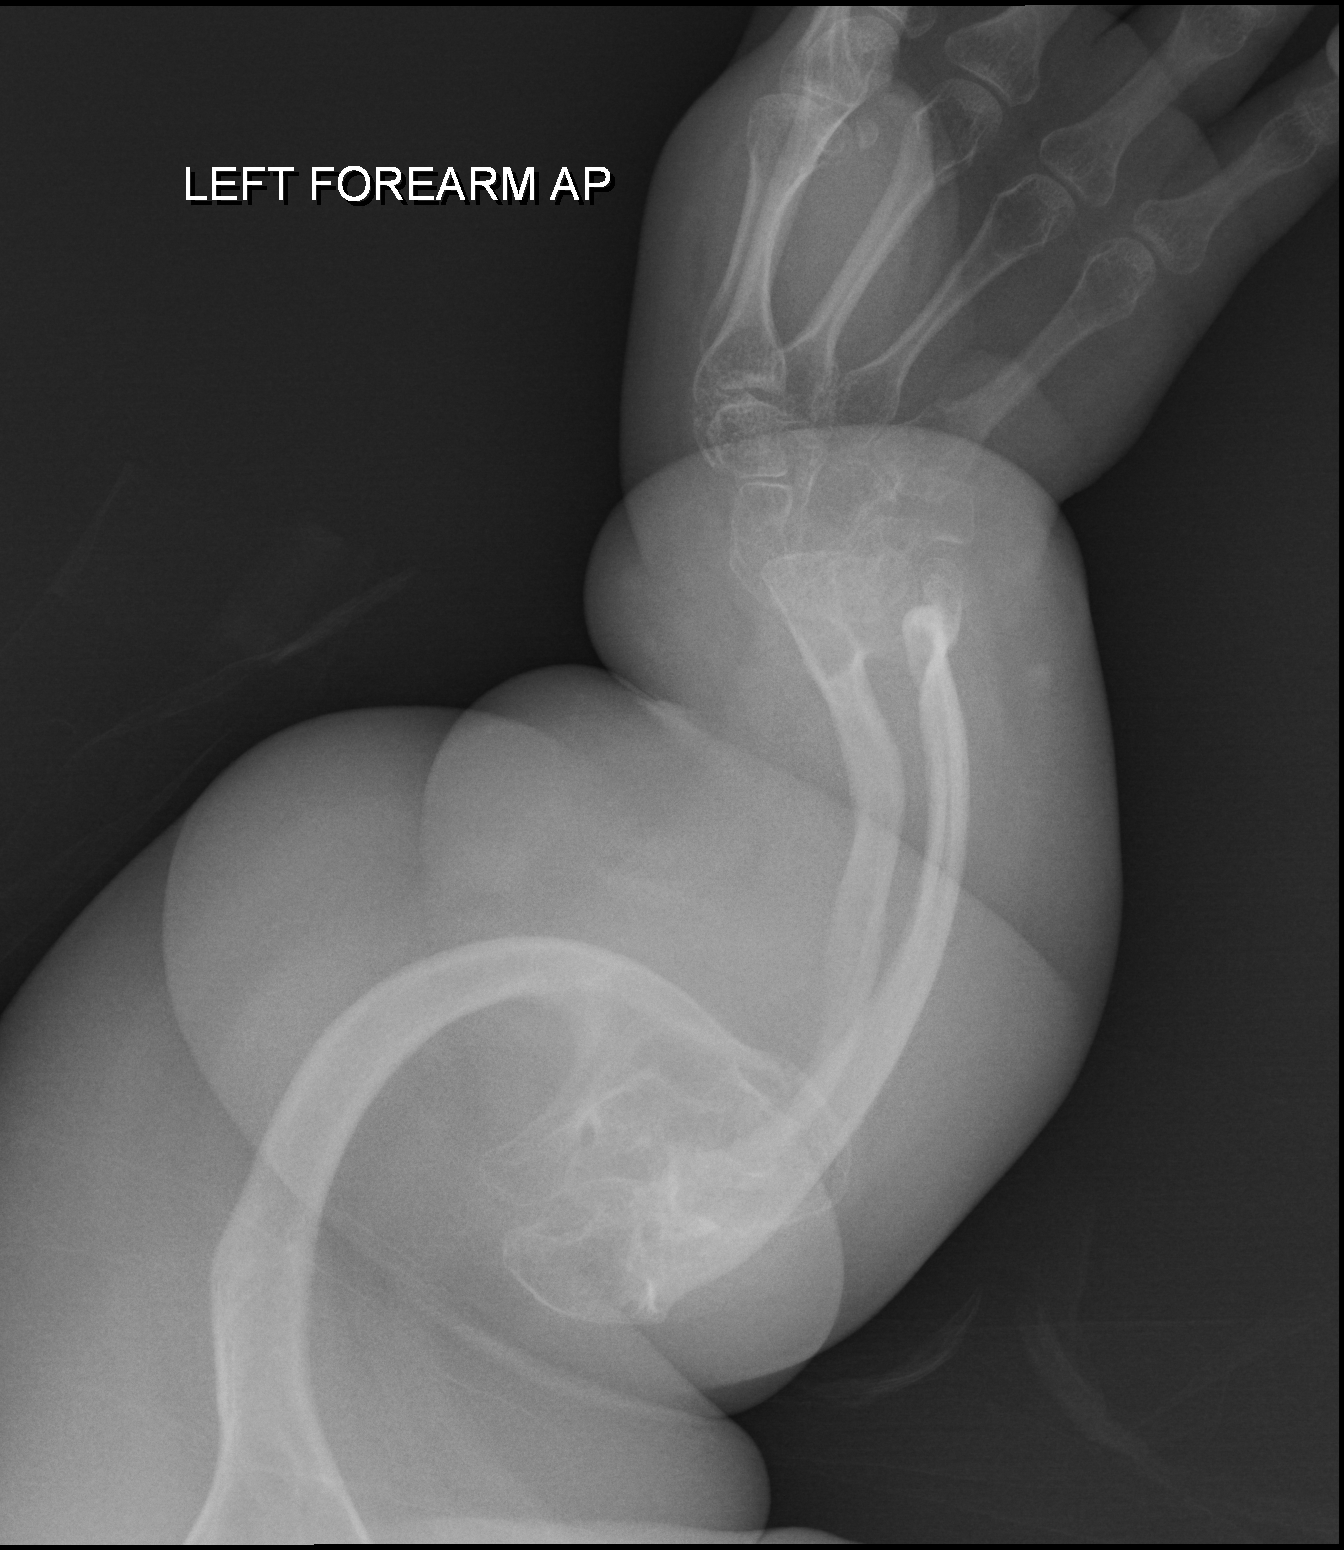

Inherited generalized disorder of connective tissue characterized by multiple fractures and blue sclera (the white of the eye) - patients suffer repeated fractures caused by the severe osteoporosis and the thin, defective cortices.

Osteogenesis Imperfecta